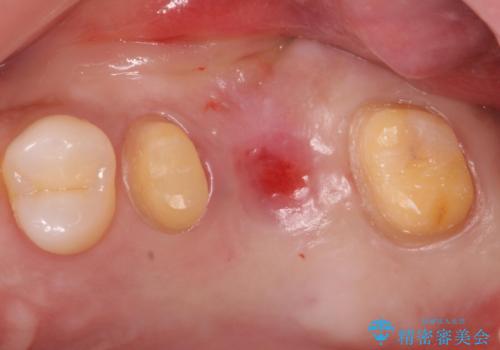

ブリッジでの修復は、抜歯後に歯がなくて噛みにくい期間が一切ありません。

歯茎の状態も良く、適合の良いブリッジを装着することができました。